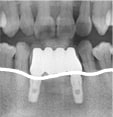

08.02.15 인공뼈

이식술 후, 사진

: 잇몸뼈 재생을 위해,

우선적으로 인공뼈이식술을

시행하였다.